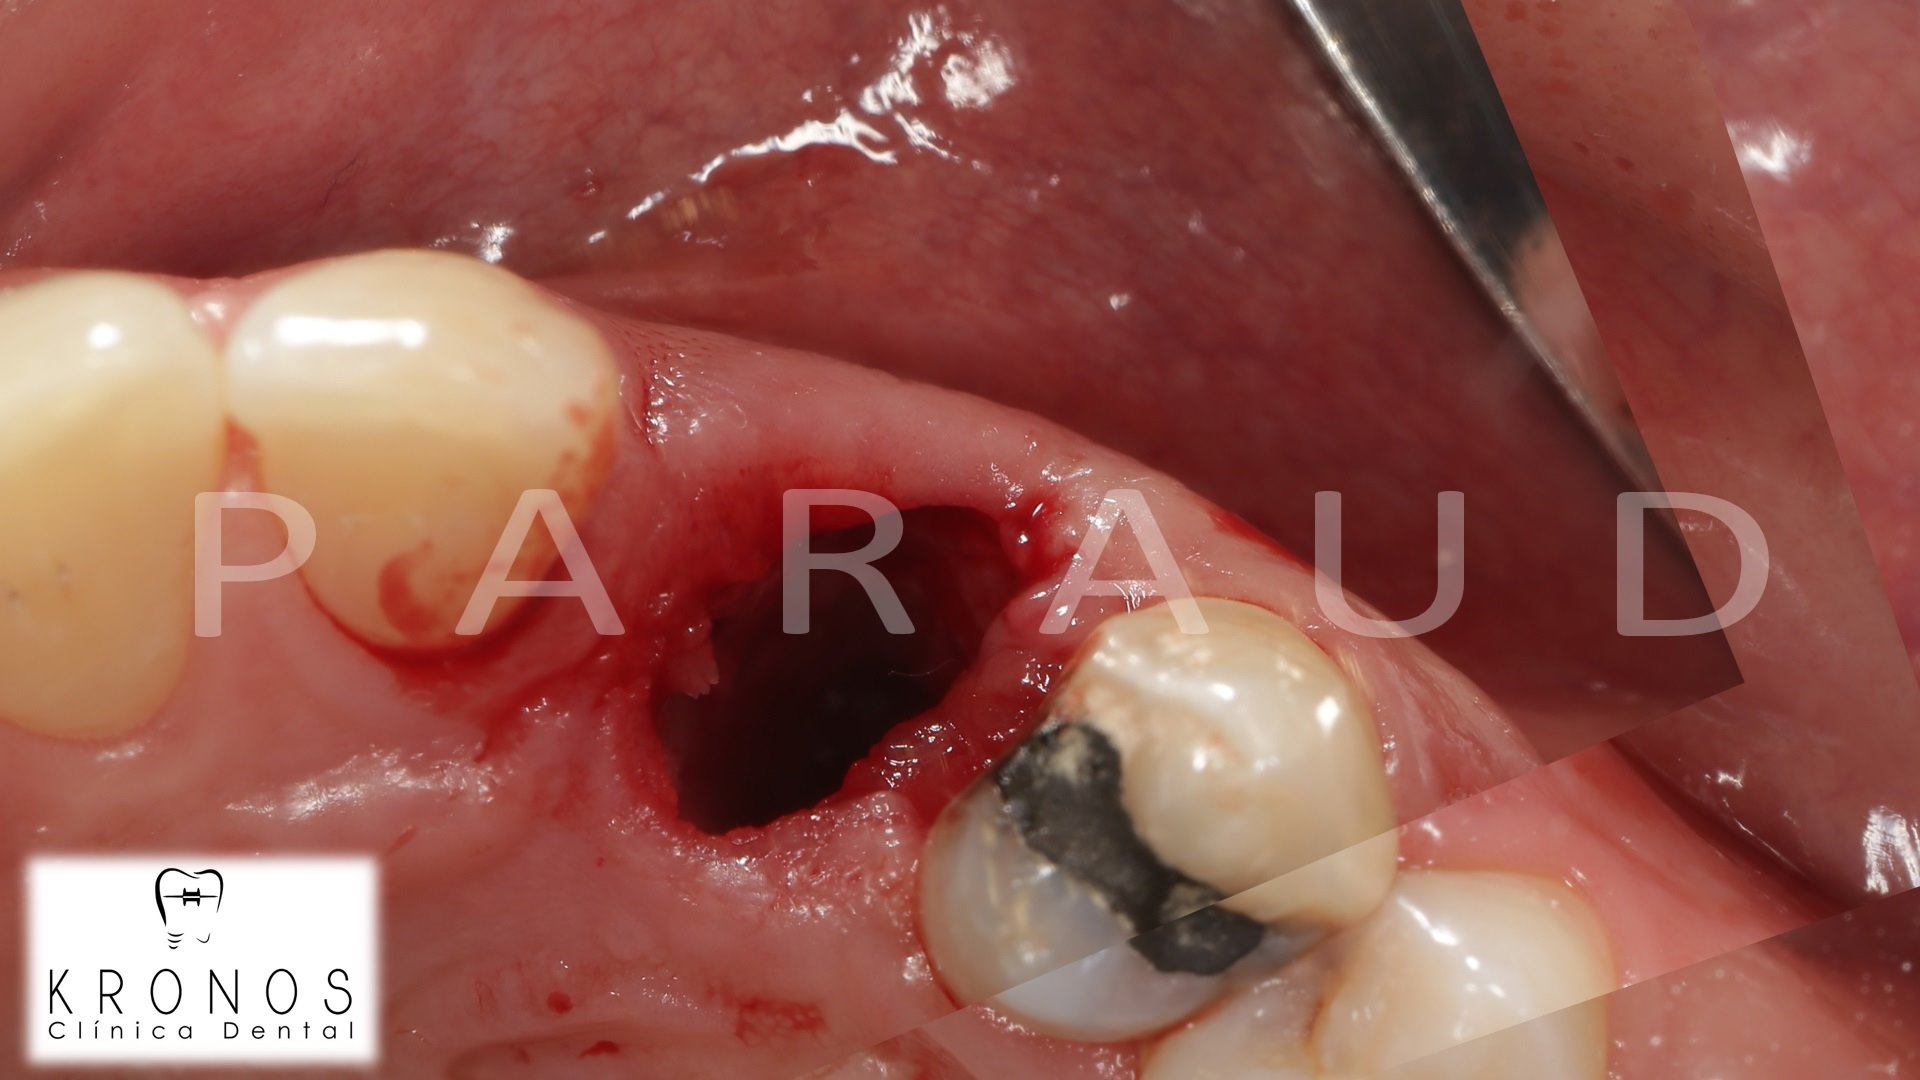

Clinical case: Digital Data Save concept in upper jaw premolar area

- Courtesy of Dr. Lysov Alexander Dmitrievich & Dr. Sofronov Matvey Vitalievich, Russia -

AnyRidge, R2GATE, R2GATE guide, ISQ value, initial stability, immediate loading, KnifeThread, maxillary posterior, #14, Digital, Dr. Lysov Alexander Dmitrievich, Dr. Sofronov Matvey Vitalievich, zirconia abutment, CAD/CAM crown

AnyRidge implant system, R2GATE, Digital prosthesis

“AnyRidge & R2GATE show stable results

after immediate extraction, immediate implant placement, & immediate loading,

even with low bone density.”